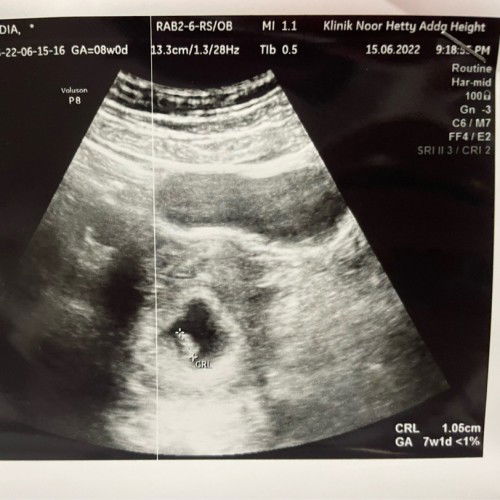

Dh dgr degupan jantung baby ye? Saya pun harini sepatutnya 7w1d taknak gi scan lg tpi sbb ada keluar light light brown skit so saya pegi scan. Alhamdulillah dah dgr degupan jantung baby tapi baby small lagi baru 6w3d. And Dr bg ubat kuatkan rahim. Ada ke mommy mommy yg mcmni jugak?

Normal. Sy scan at 6weeks bila ukur jd 5weeks 1day Tp Alhamdulillah dh nmpak janin dan heartbeat dot kecik je 💗

Normal awak, beza 1-2minggu takpe saya pun beza 5 hari….. patut dah 8w4d tapi scan 7w6d, dont worryy

normal je sis . 8week tu kalau ikut tarik period kita . kalau ukuran janin mesti dh lari sikit